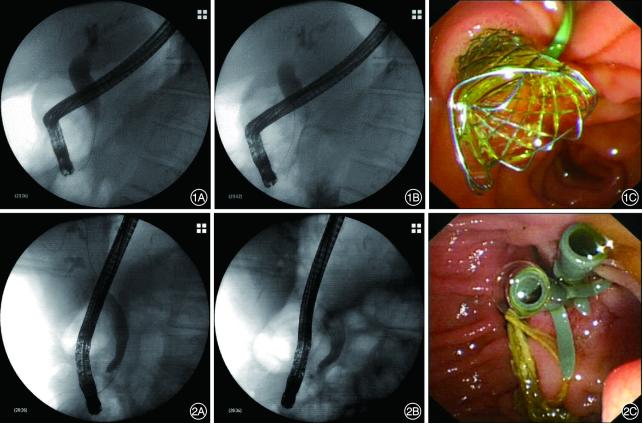

2.内镜操作:患者术前均签署知情同意书。经验丰富且具有高级职称的内镜医师经十二指肠乳头选择性胆管插管,并进行胆管造影,必要时进行胆胰管共同造影。根据患者病情,选择性行乳头扩张、狭窄段扩张、气囊/网篮取石操作。评估患者胆管狭窄的位置及长度后,根据内镜医师个人经验置入1根FCSEMS(图1)或2~3根塑料支架(图2),根据胆管狭窄程度决定支架数量。置入多根塑料支架时先插管在胆管狭窄段置入第1根塑料支架,而后退出导丝,再重新进导丝置入后续支架,支架与支架之间并列。对于插管困难或导丝反复进入胰管的患者常规行十二指肠乳头切开术和胰管支架置入术。胆管和胰管支架置入后,注入造影剂观察引流是否通畅。

图1 全覆膜金属支架治疗良性胆管狭窄 1A:经内镜逆行胰胆管造影提示胆总管下段狭窄;1B:置入全覆膜自膨式金属支架后造影,可见支架在位;1C:内镜下见支架末端位于乳头外 图2 多根塑料支架治疗良性胆管狭窄 2A:经内镜逆行胰胆管造影提示胆总管下段狭窄;2B:置入2根圣诞树塑料支架后造影,可见支架在位;2C:内镜下见圣诞树支架外口位于乳头外